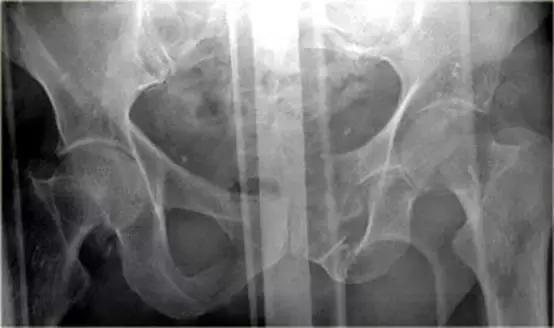

骨盆X线示耻骨骨折,膀胱区见游离骨片。

有一个指向膀胱的骨盆骨折碎片。

10%骨盆骨折伴有膀胱破裂。

最初认为膀胱破裂都是由骨盆骨折引起,但现在知道只有1/3的膀胱破裂是因为游离碎骨片造成的,另外2/3是由于剪切伤作用于膀胱造成破裂。